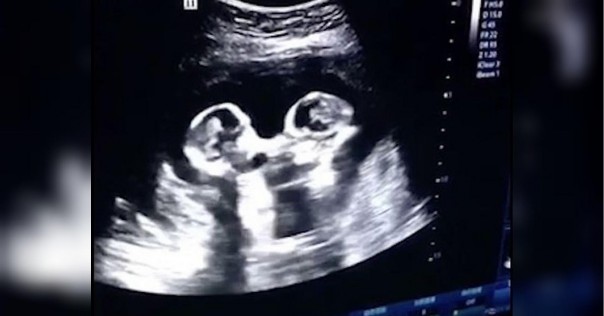

Фото Двойняшек В Утробе Матери 108 фото